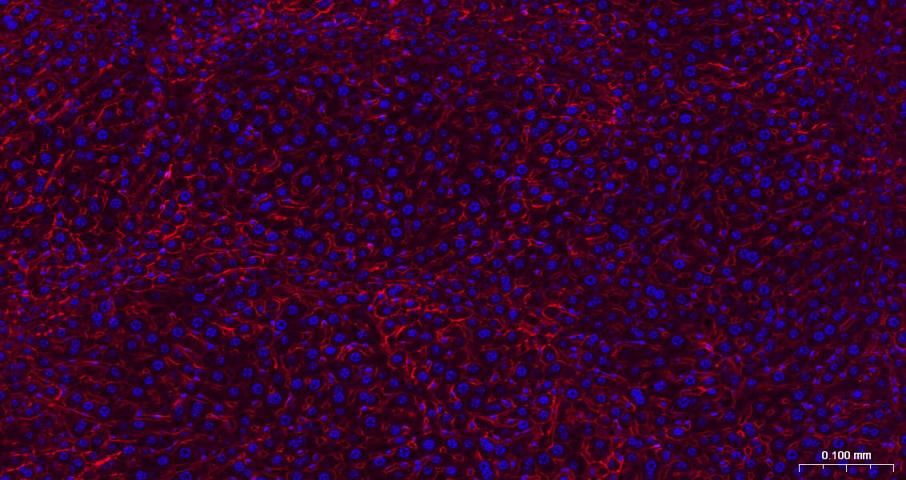

Paraformaldehyde-fixed, paraffin embedded Rat Liver; Antigen retrieval by boiling in sodium citrate buffer (pH6.0) for 15 min; The section was incubated with N Cadherin Monoclonal Antibody, Unconjugated (bsm-52389R) at 1:200 overnight at 4°C. Followed by conjugated Goat Anti-Rabbit IgG antibody (Red, bs-0295G-BF594), DAPI (blue, C02-04002) was used to stain the cell nuclei.